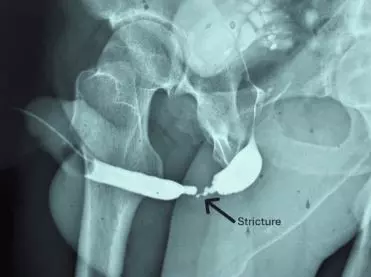

그러나 시간이 지나면서 환자에게 소변 줄기가 점점 가늘어지는 배뇨 장애가 나타나기 시작했다. 사고 발생 수년 뒤 진행된 정밀 검사에서 요도 내부 약 4cm 구간이 딱딱하게 굳어 좁아진 ‘요도 협착’이 발견됐다. 의료진은 환자의 입안 점막을 떼어 이식하는 구강 점막 이식 요도 성형술을 통해 손상된 부위를 재건했다. 수술 후 회복은 순조로웠으며, 6개월 추적 검사에서 정상적인 배뇨 흐름이 확인됐고, 협착 재발도 나타나지 않았다.